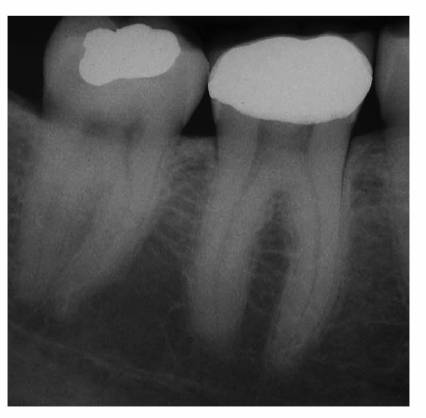

Secondary Dentin

Histologically and physiologically, there is a difference between reparative

and secondary dentin. Secondary dentin begins forming soon after the tooth

erupts into occlusion and continues to form throughout the pulp's life. This

tooth structure is deposited over the primary dentin (Figure 19-31) throughout the entire chamber and

canal in response to stimuli within the limits of normal biologic function:

mastication, light thermal changes, chemical irritants, and slight trauma. The

newly deposited dentinal tubules are smaller, exhibit more curves, and form a

protective barrier for the pulp as the size of the pulp cavity is reduced.

Reparative dentin forms as a direct response to injury. Although the deposition

is not uniform in thickness, this dystrophic calcification may completely

occlude the canal, reduce the blood supply, necrose the tissue, and complicate

the eventual endodontic therapy.

Figure 19-31: Secondary dentin represents the continuing slower circumpulpal deposition of dentin after root formation is complete.